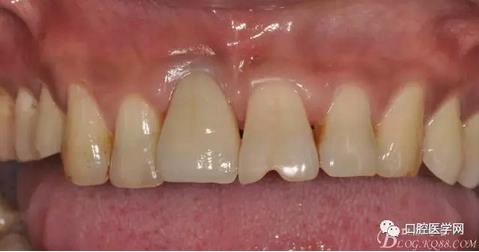

圖21 術(shù)后正位照

圖22 術(shù)后正位黑背板照